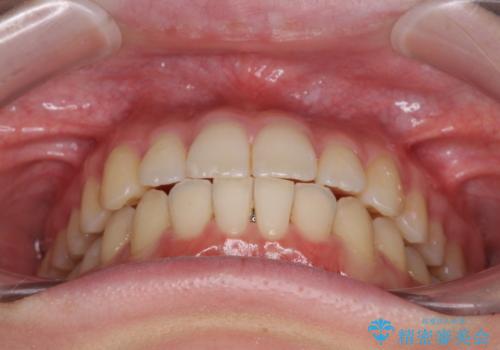

気になる前歯を整えたい インビザライン・ライトでの矯正治療

- ちょっとしたデコボコを整えたいとのことで来院された患者様です。

歯列不正は軽微であったため、インビザライン・ライトにより、費用を抑えて矯正治療を行うこととしました。

上下前歯の捻れが改善され、患者様には大変満足していただきました。